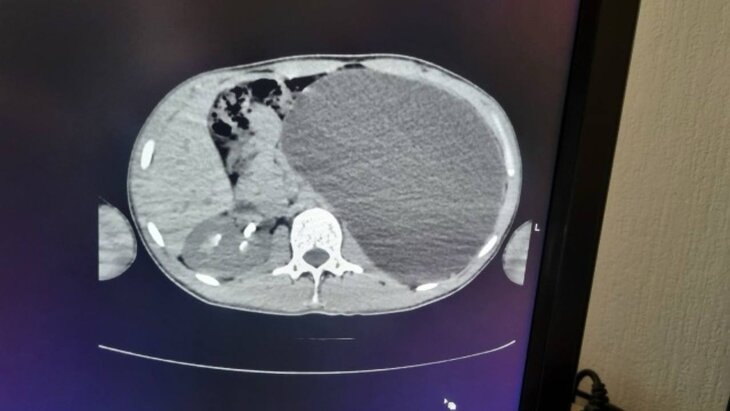

«При дальнейшем обследовании выяснилось, что у пациента гидронефроз левой почки с отсутствием паренхимы — основной ткани органа, отвечающей за его функции», — пояснила Живолуп.

«Почка нашего пациента достигла размеров пятилитровой бутылки, занимая почти весь живот и сдавливая соседние органы. Это была настоящая бомба замедленного действия: любая травма или удар могли привести к разрыву органа», — добавили в ДГКБ №1.